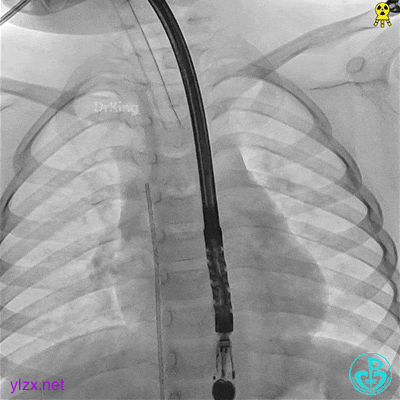

DSA下建立轨道

导管送至左心房中部。

送入加硬导丝至左上肺静脉。

送入封堵器

鞘管沿着导丝送入左房。

前推钢缆,送入封堵器。